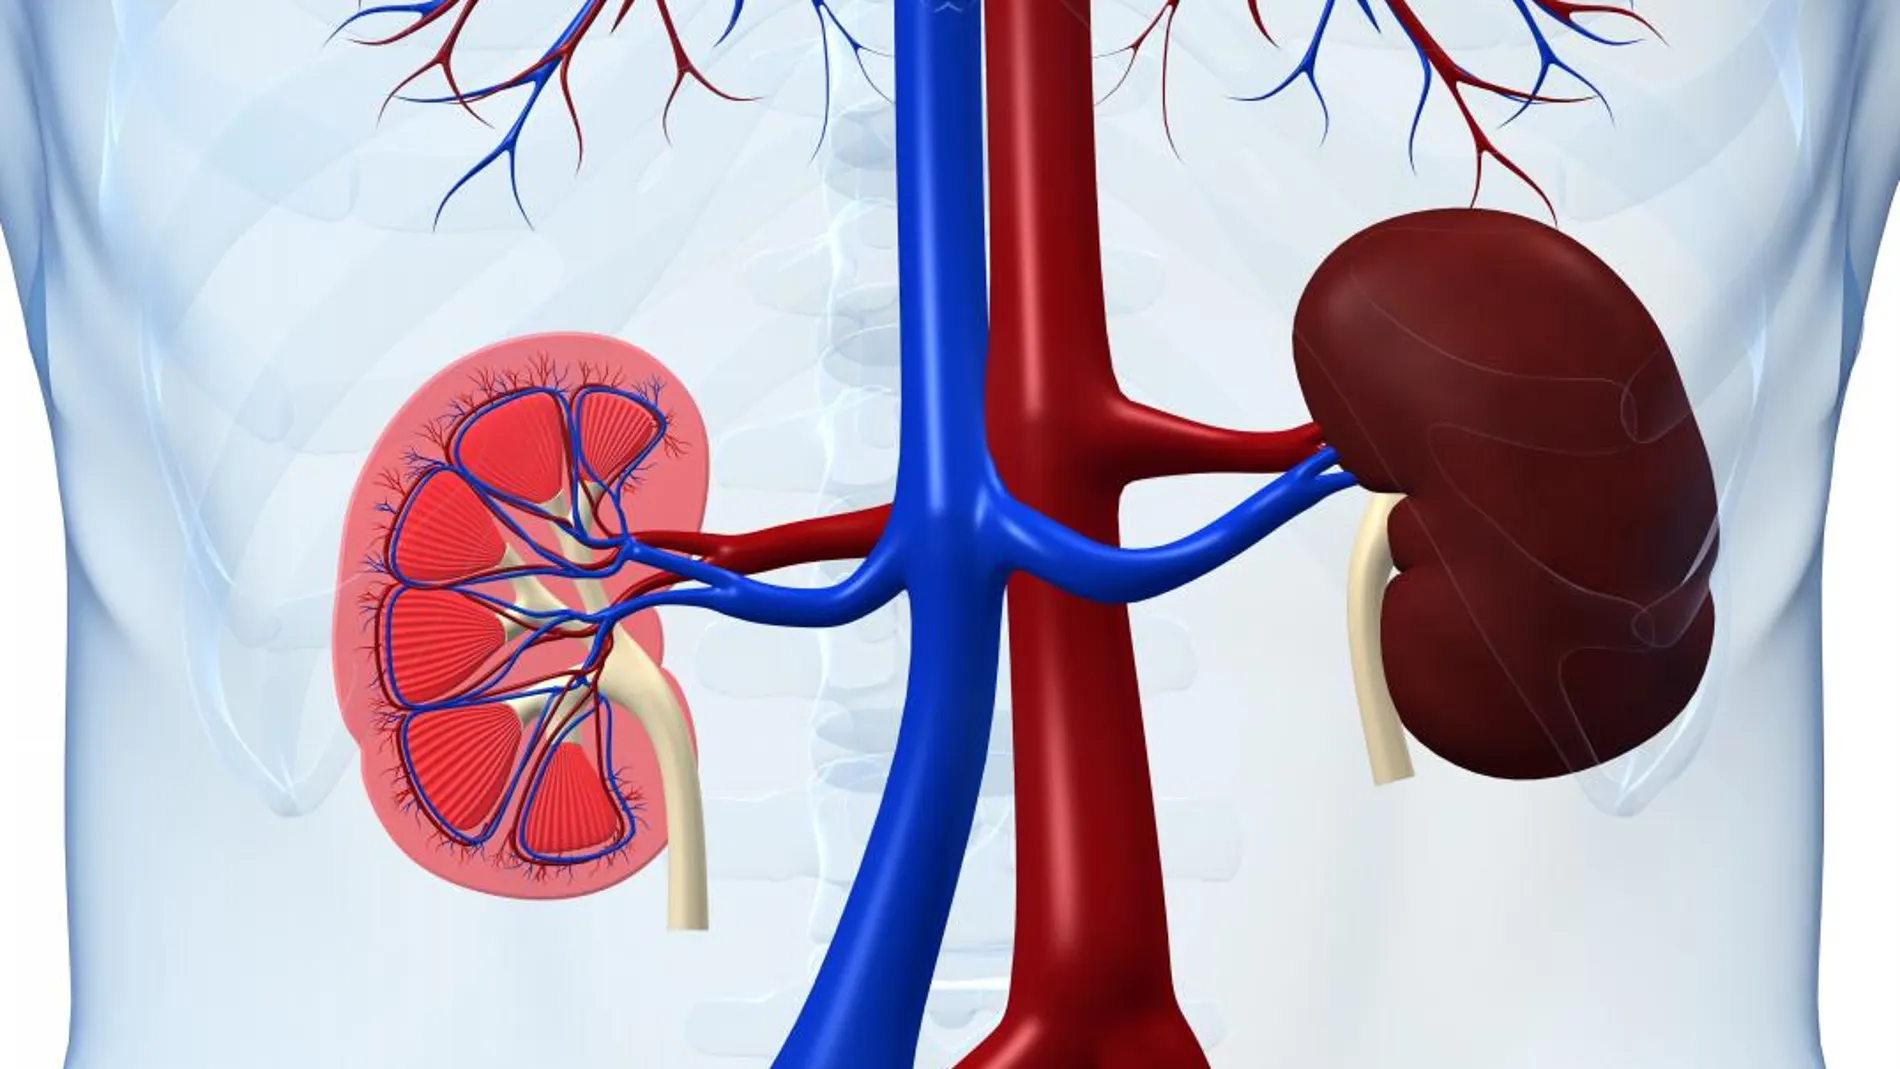

“España ha frenado un proyecto de tráfico de órganos que quería instalarse en Europa”, ha afirmado la directora de la Organización Nacional de Trasplantes (ONT), Beatriz Domínguez-Gil, durante la Reunión Nacional de Coordinadores de Trasplantes y Profesionales de la Comunicación. El programa estadounidense al que se refiere se llama Global Kidney Exchange y está avalado por el Nobel de Economía Alvin Roth, “con el que tuve que reunirme para decirle que lo que planteaba era tráfico de órganos”. ¿Cómo trabaja este programa? Como explicó la nefróloga, “se invita” a parejas de países pobres a viajar a Estados Unidos -único país en el que se ha hecho hasta el momento- para facilitar una cadena de trasplantes de riñón, para no tener que tener en cuenta si es compatible o no con una pareja concreta. Se le ofrece el pago del viaje, del trasplante, de la estancia, de todos los gastos médicos, “así como diez años de medicamentos inmunosupresores”, explica la directora. Cuando termina el proceso la pareja extranjera regresa a su país, “donde no se le garantiza el cuidado y seguimiento necesario tras esta intervención”. Por ello, la responsable de la ONT tiene claro que “es una forma encubierta de compraventa de órganos. Es un pago en especie, una cosificación de la persona y, por supuesto, un ahorro en hemodiálisis para Estados Unidos donde este tratamiento es muy costoso”. Ya se han efectuado cuatro trasplantes con esta “agencia”: dos personas llegaron de Filipinas y otras dos de México.